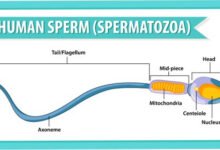

كتاب الاعجاز محور علم الأمشاج

تحميل كتاب الاعجاز محور علم الأمشاج